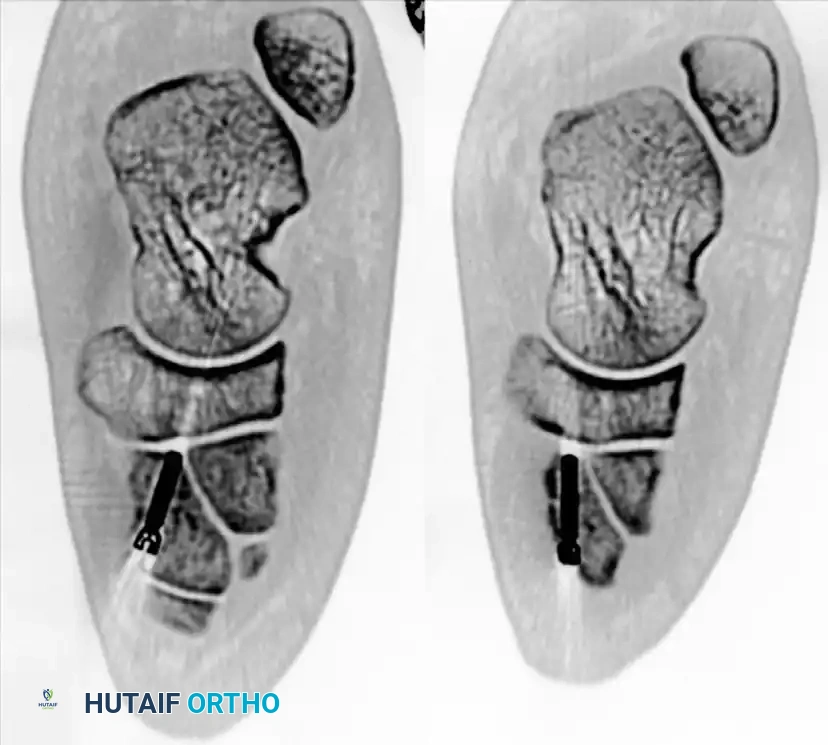

FIGURE 5: Postoperative axial CT scan verifying the precise intraosseous trajectory of the fixation screws and the anatomic restoration of the medial cuneiform and TMT articulations.